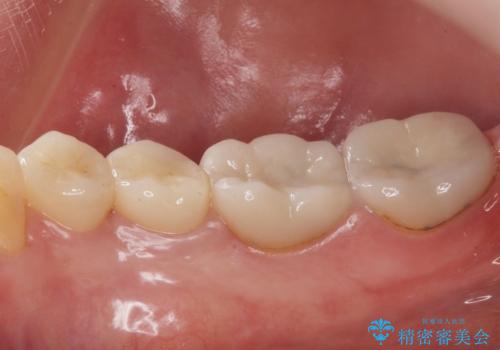

- 右下45:仮歯+ジルコニアクラウン/11,000円+110,000円費用は治療当時の料金となります

樹脂の材料と歯の境界部分は虫歯・着色の好発部位となります。

度重なる治療で継ぎ接ぎになってしまった場合はクラウンで歯を覆った方が虫歯・着色のリスクを減らすことができます。